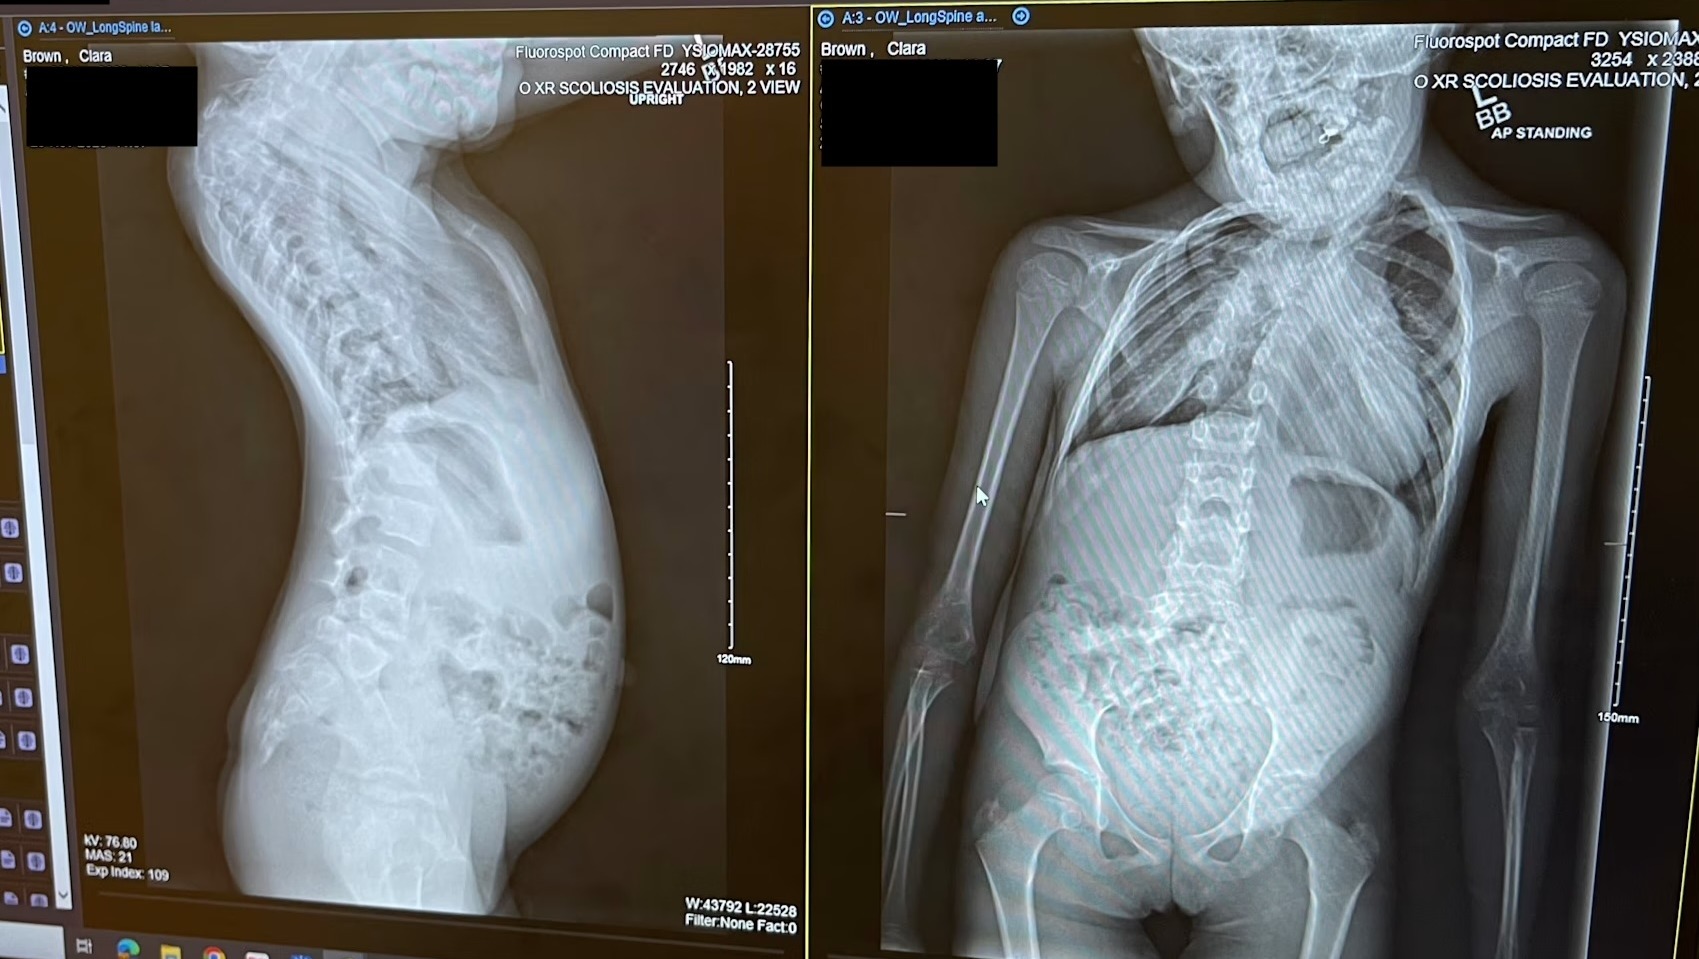

Clara was born with severe scoliosis, with several fused and missing vertebrae in her cervical and thoracic spine, and missing ribs. Her spinal cord is also kinked just below the neck. Simply put, Clara has an incredibly complex core bone structure that has impacted several of her body’s systems, including neurologic damage and severely decreased lung function. The spinal team at Seattle Children’s has 3D-printed Clara’s spine to study and plan the safest approach.

Traction: Clara will be admitted into Seatle Children’s Hospital in early May to be placed in halo gravity traction, a metal ring attached to her skull that applies gradual tension to her spine over several weeks in the hospital. This allows slow correction so her spinal cord can adapt safely. She will be closely monitored neurologically, with frequent imaging.

Vertebral Separation: There may be a second surgery to separate fused vertebrae if necessary. This will be determined once she is in traction.

Spinal Fusion: The final and most complex surgery involves removing the apex of the deformity and placing rods to stabilize the spine.